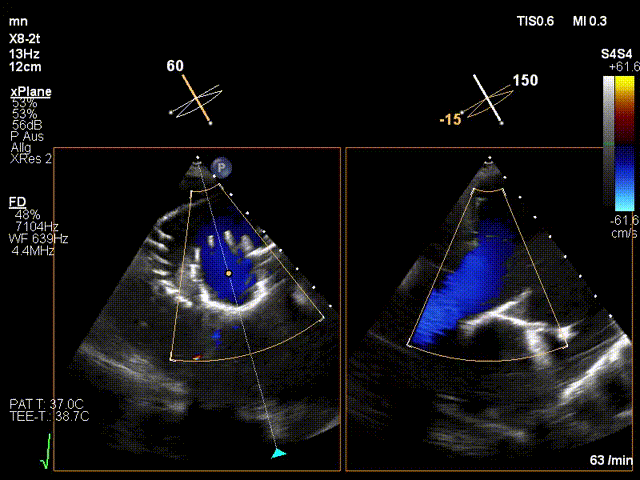

近日,德國慕尼黑大學(xué)Jörg Hausleiter教授團(tuán)隊(duì)成功應(yīng)用LuX-Valve Plus經(jīng)血管三尖瓣置換系統(tǒng)救治了一例因三尖瓣大量反流導(dǎo)致的右心衰竭患者,術(shù)后超聲顯示人工三尖瓣位置固定滿意,瓣架穩(wěn)定,無反流和瓣周漏?;颊咴谑中g(shù)室即刻拔除氣管插管,血流動(dòng)力學(xué)改善顯著,LuX-Valve Plus經(jīng)血管三尖瓣置換系統(tǒng)的治療效果優(yōu)異。

手術(shù)在全麻狀態(tài)下進(jìn)行。在加拿大圣保羅醫(yī)院的Anson Cheung教授的指導(dǎo)參與下,術(shù)者采用經(jīng)右側(cè)頸靜脈入路的方式將輸送器送入患者心臟內(nèi),在TEE及DSA引導(dǎo)下調(diào)整輸送器頭端角度,使得輸送器與三尖瓣瓣環(huán)平面垂直。在輸送器進(jìn)入右心室后釋放室間隔錨定裝置,而后釋放瓣葉夾持件(2個(gè)耳片結(jié)構(gòu))成垂直狀態(tài)。在TEE及DSA確定夾持件固定至三尖瓣葉根部且位于右室側(cè)后釋放人工瓣心房側(cè)盤片。隨后調(diào)整瓣膜同軸性以及室間隔錨定件位置(貼合室間隔),前推藏針管并固定,進(jìn)而釋放室間隔錨定裝置,并再次確認(rèn)瓣膜位置、穩(wěn)定性及同軸性,合攏輸送鞘后撤出輸送器,完成LuX-Valve Plus人工三尖瓣瓣膜的植入。

LuX-Valve Plus經(jīng)血管三尖瓣置換系統(tǒng)本次“出海”圓滿完成,術(shù)后Jörg Hausleiter教授對(duì)LuX-Valve Plus經(jīng)血管三尖瓣置換系統(tǒng)的器械性能和治療效果大為稱贊,認(rèn)為LuX-Valve Plus的手術(shù)體驗(yàn)非常好。術(shù)后即刻超聲顯示三尖瓣反流消失,血流動(dòng)力學(xué)改善顯著,患者恢復(fù)快。Anson Cheung教授也肯定了LuX-Valve Plus術(shù)中操作的便捷性,認(rèn)為LuX-Valve Plus容錯(cuò)率高,對(duì)術(shù)中影像的依賴較小,后期希望可以更多的應(yīng)用LuX-Valve Plus三尖瓣置換系統(tǒng)于臨床實(shí)踐,讓更多的三尖瓣重度反流患者盡早獲益,改善預(yù)后。